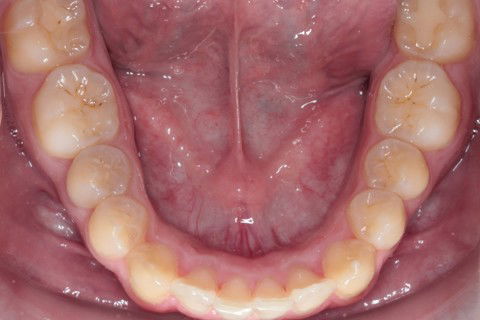

Final Ocl. Inf

Paciente: Sexo masculino, 16 anos

Sugestão de Tratamento: Tratamento ortodôntico com o uso do sistema de alinhadores removíveis Invisalign. Sem extrações dentarias, pois o perfil do paciente não era favorável. Por ser um paciente jovem, optou-se por uma expansão dentária controlada, buscando a remodelamento dos arcos.

1º Passo: Planejamento Digital com software Clincheck;

2º Passo: Confecção de 36 alinhadores personalizados conforme planejamento;

3º Passo: Evolução do tratamento que teve duração total de 18 meses, com a utilização de elástico de Classe II;

4º Passo: Checklist Oclusal + Fotografias finais.

Obs: Nesse caso não foi utilizado alinhadores adcionais para refinamento.